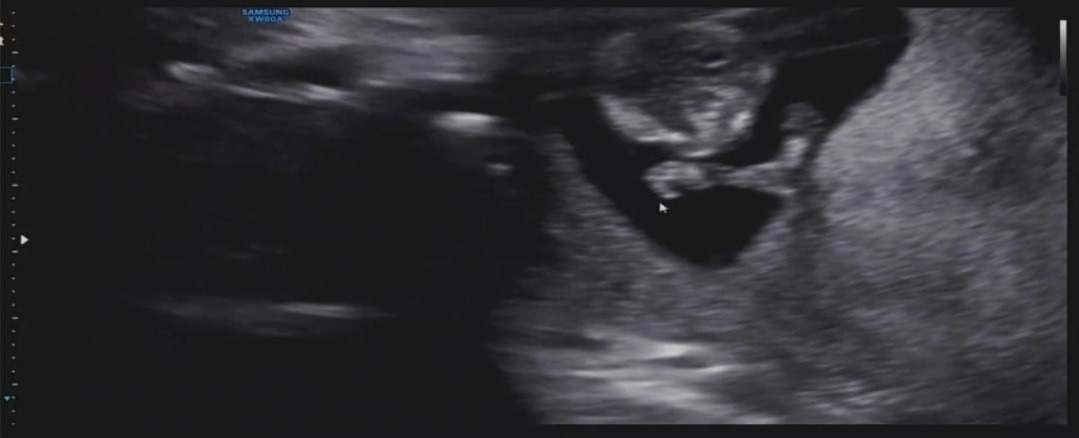

아기가 엄마 뱃속에서 폴짝 뛰는 모습이다. 4주 만에 본 초음파 사진은 벌써 저렇게 커진 아기를 확인할 수 있었다. 키는 벌써 4.83cm나 자라서 엄마 뱃속에서 열심히 운동도 하면서 크고 있는 것 같다. 삼 등신 형태가 자리 잡혀서 이제 제법 사람 모습을 하고 있어 볼수록 신기하다. 자세히 보면 등뼈와 손가락뼈도 보이는 게 꼬물꼬물 아주 귀엽다.

보통 11주에서 13주 차에 1차 기형아 검사를 받게 된다. 우리 부부는 이번 11주 차에 시행했다. 검사는 목 투명대, 혈액검사로 진행을 한다. 목 투명대는 초음파로 진행하는데 아가의 목 뒷덜미에 있는 투명한 막 같은 것을 관찰하는 것이다. 이 막의 두께가 3mm가 넘으면 염색체 이상을 의심해 볼 수 있다. 그때는 양수검사를 생각해야 한다. 우리 아가는 다행히 0.64mm로 문제가 없는 것으로 나왔다.